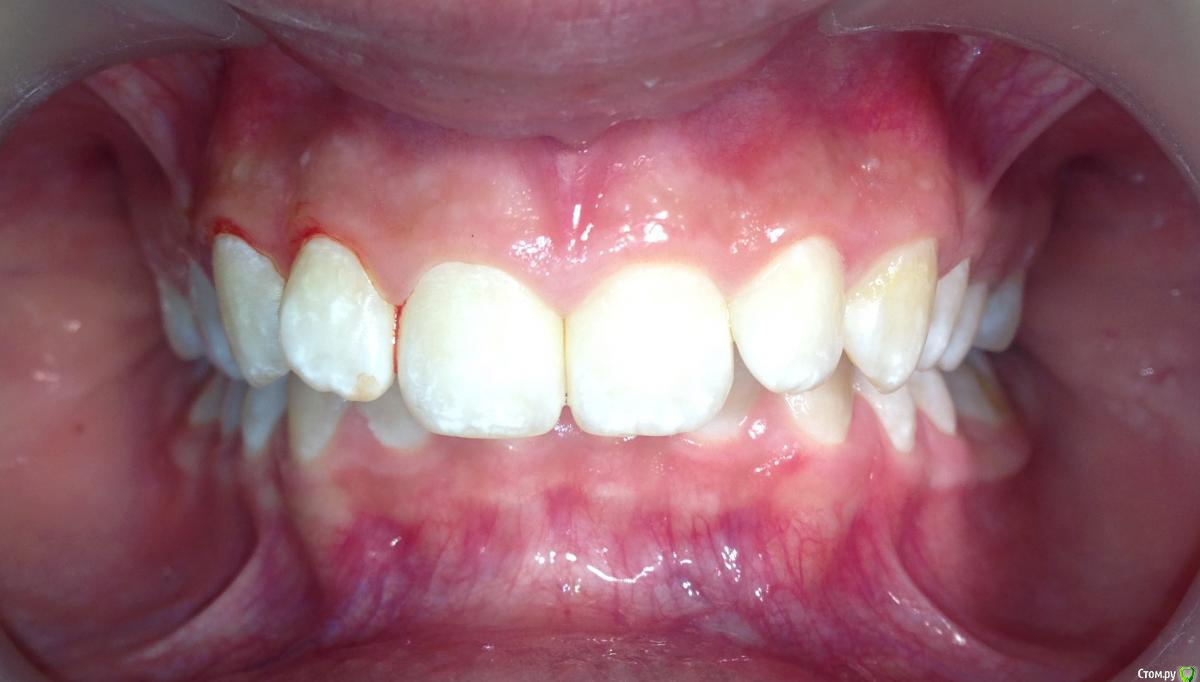

post-38874-0-87186300-1459536185_thumb.jpgpost-38874-0-15339500-1459536188_thumb.jpgpost-38874-0-82577500-1459536190_thumb.jpgpost-38874-0-61079300-1459536193_thumb.jpgpost-38874-0-22178300-1459536196_thumb.jpgpost-38874-0-56404400-1459536198_thumb.jpgpost-38874-0-43380300-1459536199_thumb.jpgpost-38874-0-04081600-1459536228_thumb.jpgpost-38874-0-34503200-1459536230_thumb.jpgpost-38874-0-34236500-1459536233_thumb.jpgpost-38874-0-95387400-1459536234_thumb.jpgpost-38874-0-86290600-1459536242_thumb.jpgpost-38874-0-47956700-1459536252_thumb.jpgpost-38874-0-98507600-1459536273_thumb.jpgpost-38874-0-52220700-1459536283_thumb.jpgpost-38874-0-12327700-1459536263_thumb.jpg

Извините за качество фото.

Пациентка 14 лет. Было принято решение лечить без удаления, тк. профиль не позволяет да и ретропозиция нч. Лечение идет. Я назначила ранние эластики слабые, на 17/25 нити на вч и 18 нити на нч. по 2 классу короткие 3,4-4,5. Пациентка пришла через месяц жалуется на щелканье челюсти во время ношения эластиков и сразу после их снятия. Т.е. если открывает рот, то челюсть скачкообразно двигается и щелчками. Последние 2 недели, когда много говорит, то вообще стала заедать. Это она так сказала. После отмены эластиков (страшно), через неделю пришла, рот открывает ровно, без девиации, щелчков нет. Вопрос: почему щелкает и что с этим делать? По поводу прикуса, посоветуйте, пожалуйста, как нормализовать? Аппарат типа гербста? может ей твинблок сделать? Эластики? К сожалению другими методами я пока что не владею. Спасибо, очень жду ваших советов.